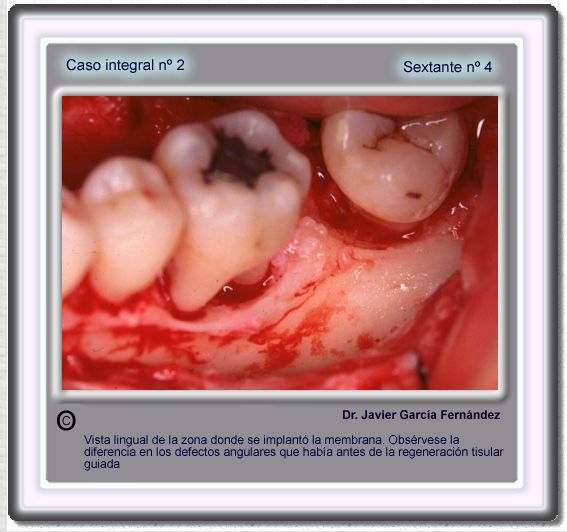

image 68